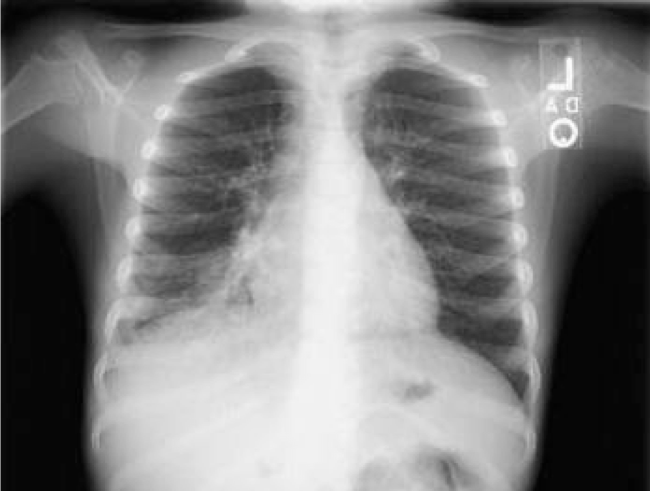

how do you determine if penetration is adequate in a PA CXR

YOU SHOULD BE ABLE TO SEE THE THORACIC SPINE THROUGH THE HEART SHADOW Inspiration: should see at least 8-9 posterior ribs

how do you determine if inspiration is adequate in a PA CXR

Inspiration: should see at least 8-9 posterior ribs

how do you determine if rotation is adequate in a PA CXR

rotation: spinous process should fall equidistant b/w the medial ands of the clavicle

how do you tell the adequacy of a cxr

RIP MA rotation inspiration penetration magnification angulation

what are the problems with poor rotation

significant rotation may alter expected contours of the heart and great vessels, the hila and the hemidiaphragms